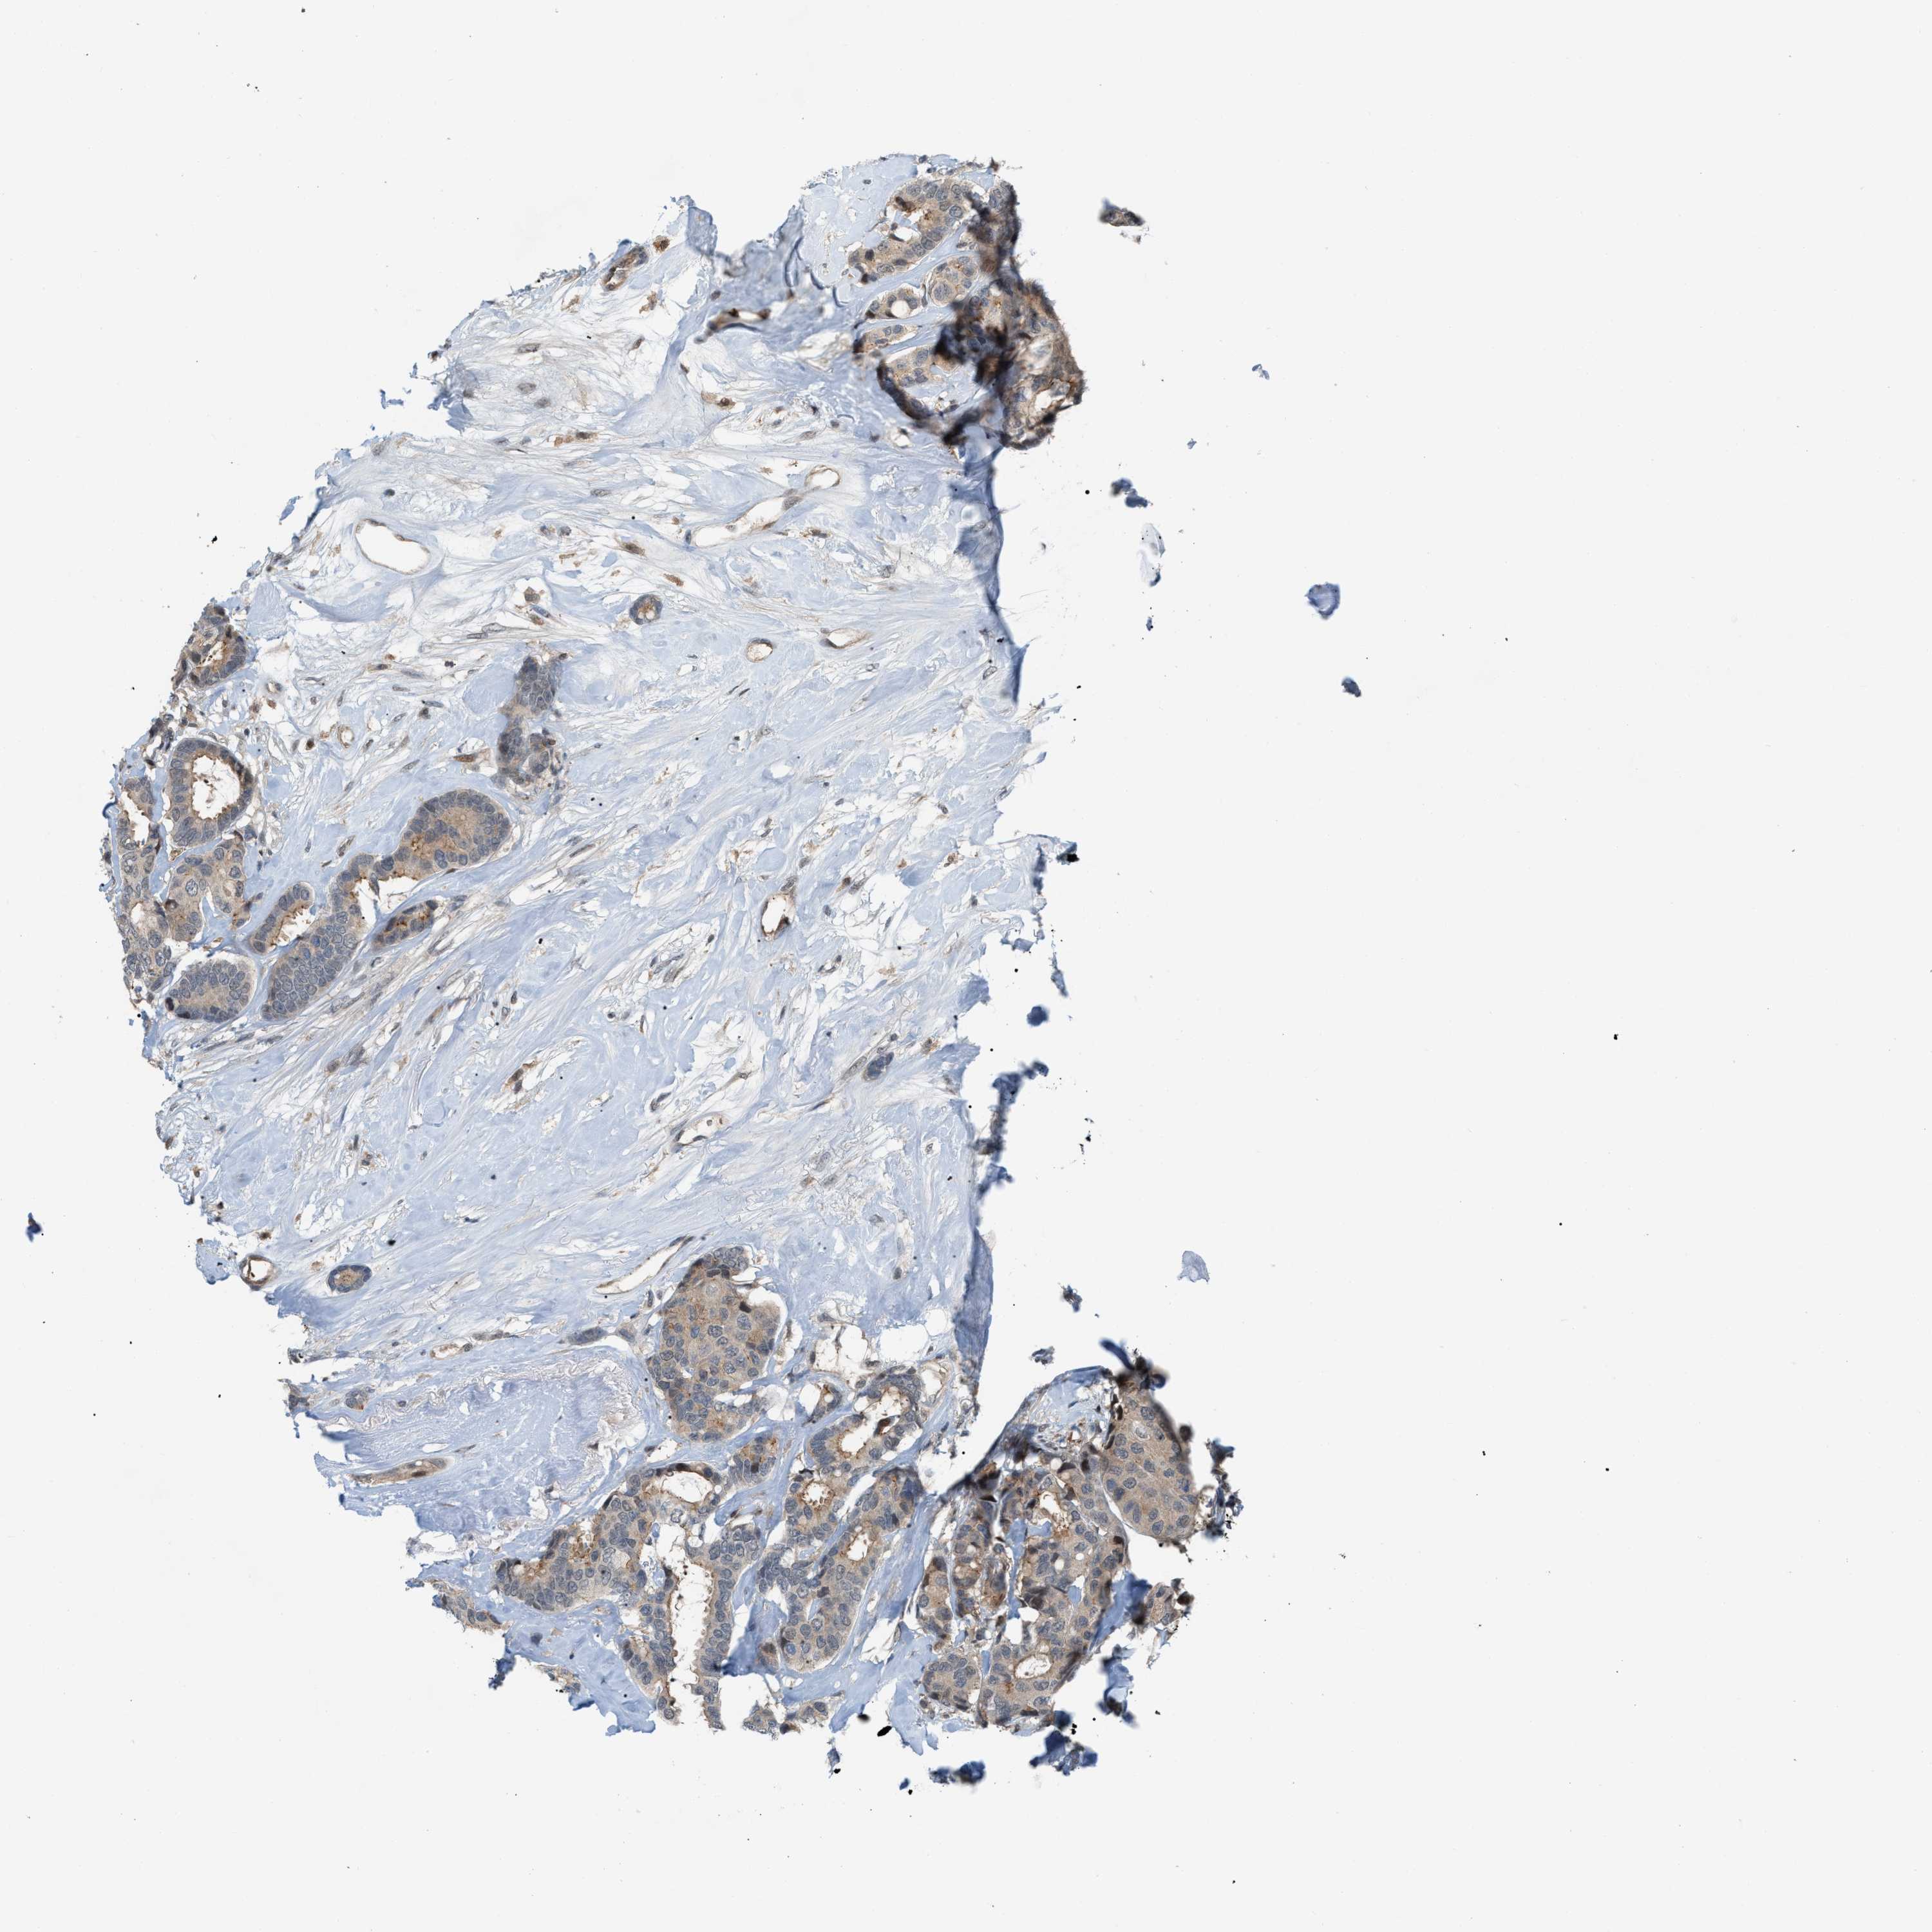

BRCA TCGA BRCA VALIDATION PROTEIN EXPRESSION

ANTIBODIES

AND

VALIDATION